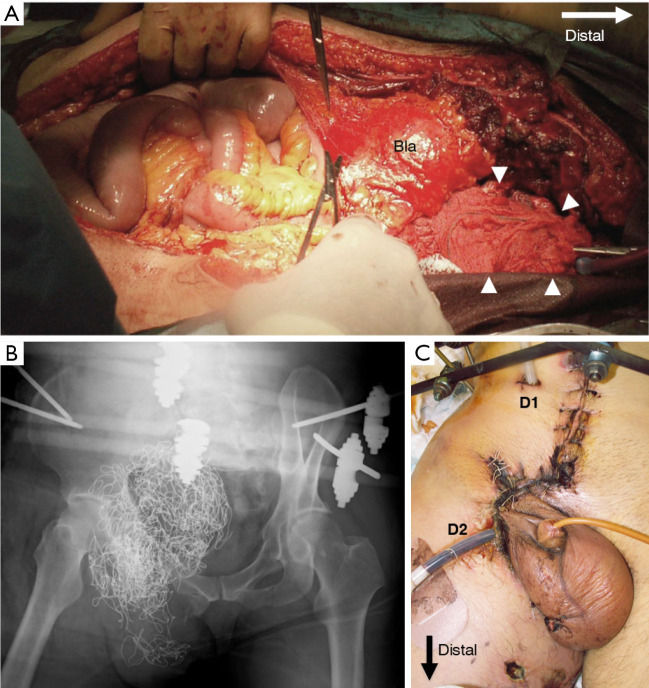

Case description: A healthy 41-year-old man presented with an open pelvic ring fracture and a laceration in the lower abdomen sustained at an ironworks. His hemodynamic status was unstable. Pelvic ring stabilization with an external fixator, ligation of the median sacral and bilateral internal iliac arteries, partial resection of the ileum, appendectomy, and intra-abdominal pelvic packing were performed. Seven days after the injury, he developed a single spike fever of 39.8 ℃ with a significant pus discharge from the open wound around his groin. A computed tomography scan revealed an accumulation of gas around the sacroiliac joint, in the abdominal cavity, and the adductors and gluteus maximus muscles caused by non-clostridial gas gangrene. We performed surgical debridement three times and initiated vancomycin administration. Hyperbaric oxygen therapy was also initiated as an adjunctive therapy. The patient could walk with a cane 5 months after the injury.

Conclusions: We described a multidisciplinary case of a patient with a Wang type II open pelvic fracture who required emergent damage control and subsequently developed anaerobic sepsis. Bleeding was controlled by packing gauze into the intraperitoneal cavity and applying external fixation to the pelvic ring. However, it is important to administer prophylactic antibiotics against anaerobic bacteria and to detect subsequent infections early when packing gauze into the intraperitoneal cavity in patients with open pelvic fractures.